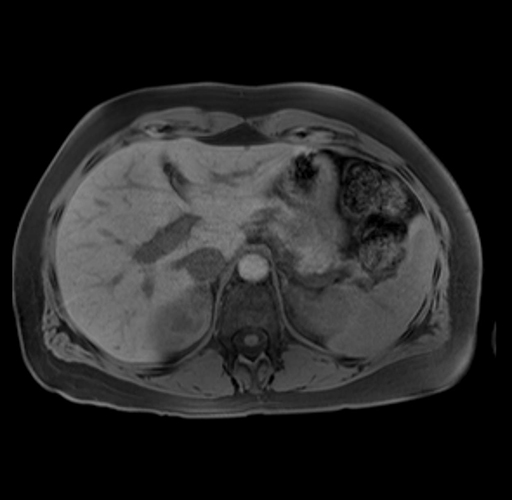

Imaging Analysis

Look through the patient's CT scan to identify any areas of concern for the necessary procedure.

Based on your CT findings, which issue(s) are present and would give reason for "planned slowing down moment(s)" in this case?